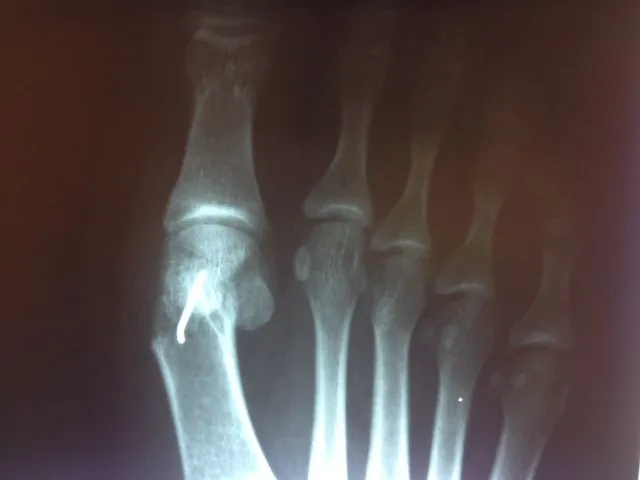

In the x-ray image below is a Hallux Valgus or what is more commonly known as a bunion deformity where the great toe is deviated towards the lesser toes causing abnormal structure which is a result of genetics, abnormal shoegear and abnormal mechanics will cause wearing of the joint and enlargement of the head of the long bone called the first metatarsal.

Post-surgical repair of the same patient bunion deformity with the great toe now in rectus (straight) position with surgically placed screws in the head of the first metatarsal that were used to secure fixation of the cut made across the bone to translate the head of the bone laterally in order to reduce the deformity. The screws will remain in place even after the bone heals.